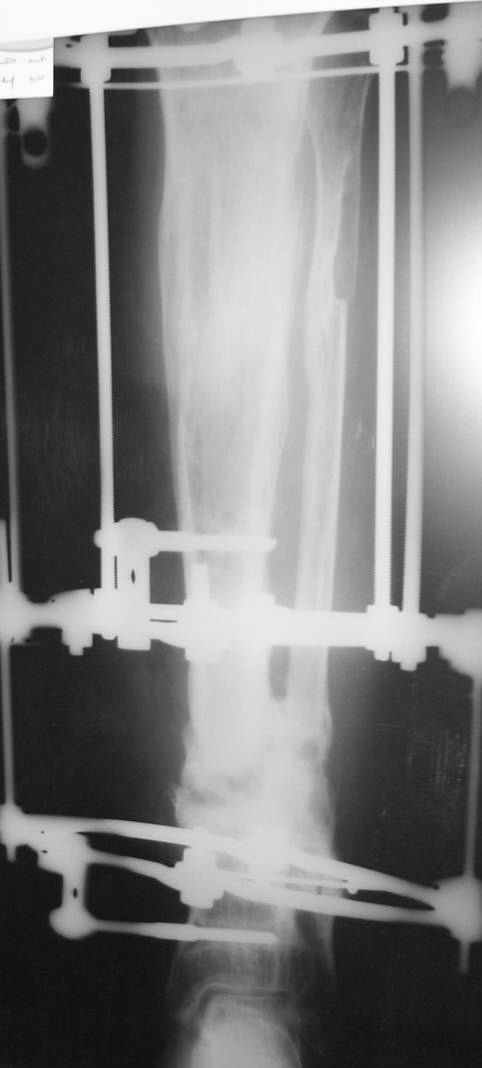

This Patient have to be treated by using Ilizarov bifocal bone transport, aproximatly as showen here.

It is difficult to see on the xr you sent, but it seems that proximal and distal metaphysis are also involved and the bone there is not of good quality too do a bifocal convergent transport.

Alternative will be to do a medial transport of half or of the all fibula after ressection of all bad quality bone as on the attached scketch.